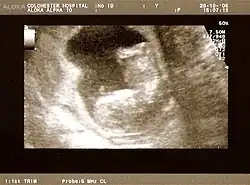

Obstetric ultrasonography is routinely used for dating the gestational age of a pregnancy from the size of the fetus, determine the number of fetuses and placentae, evaluate for an ectopic pregnancy and first trimester bleeding, the most accurate dating being in first trimester before the growth of the foetus has been significantly influenced by other factors.[22] Ultrasound is also used for detecting congenital anomalies (or other foetal anomalies) and determining the biophysical profiles (BPP), which are generally easier to detect in the second trimester when the foetal structures are larger and more developed.[23]

X-rays and computerized tomography (CT) are not used, especially in the first trimester, due to the ionizing radiation, which has teratogenic effects on the foetus.[24] No effects of magnetic resonance imaging (MRI) on the foetus have been demonstrated,[25] but this technique is too expensive for routine observation. Instead, obstetric ultrasonography is the imaging method of choice in the first trimester and throughout the pregnancy, because it emits no radiation, is portable, and allows for realtime imaging.[26]

The safety of frequent ultrasound scanning has not been confirmed. Despite this, increasing numbers of women are choosing to have additional scans for no medical purpose, such as gender scans, 3D and 4D scans.[27] A normal gestation would reveal a gestational sac, yolk sac, and fetal pole.[28]

The gestational age can be assessed by evaluating the mean gestational sac diameter (MGD) before week 6, and the crown-rump length after week 6. Multiple gestation is evaluated by the number of placentae and amniotic sacs present.[29]